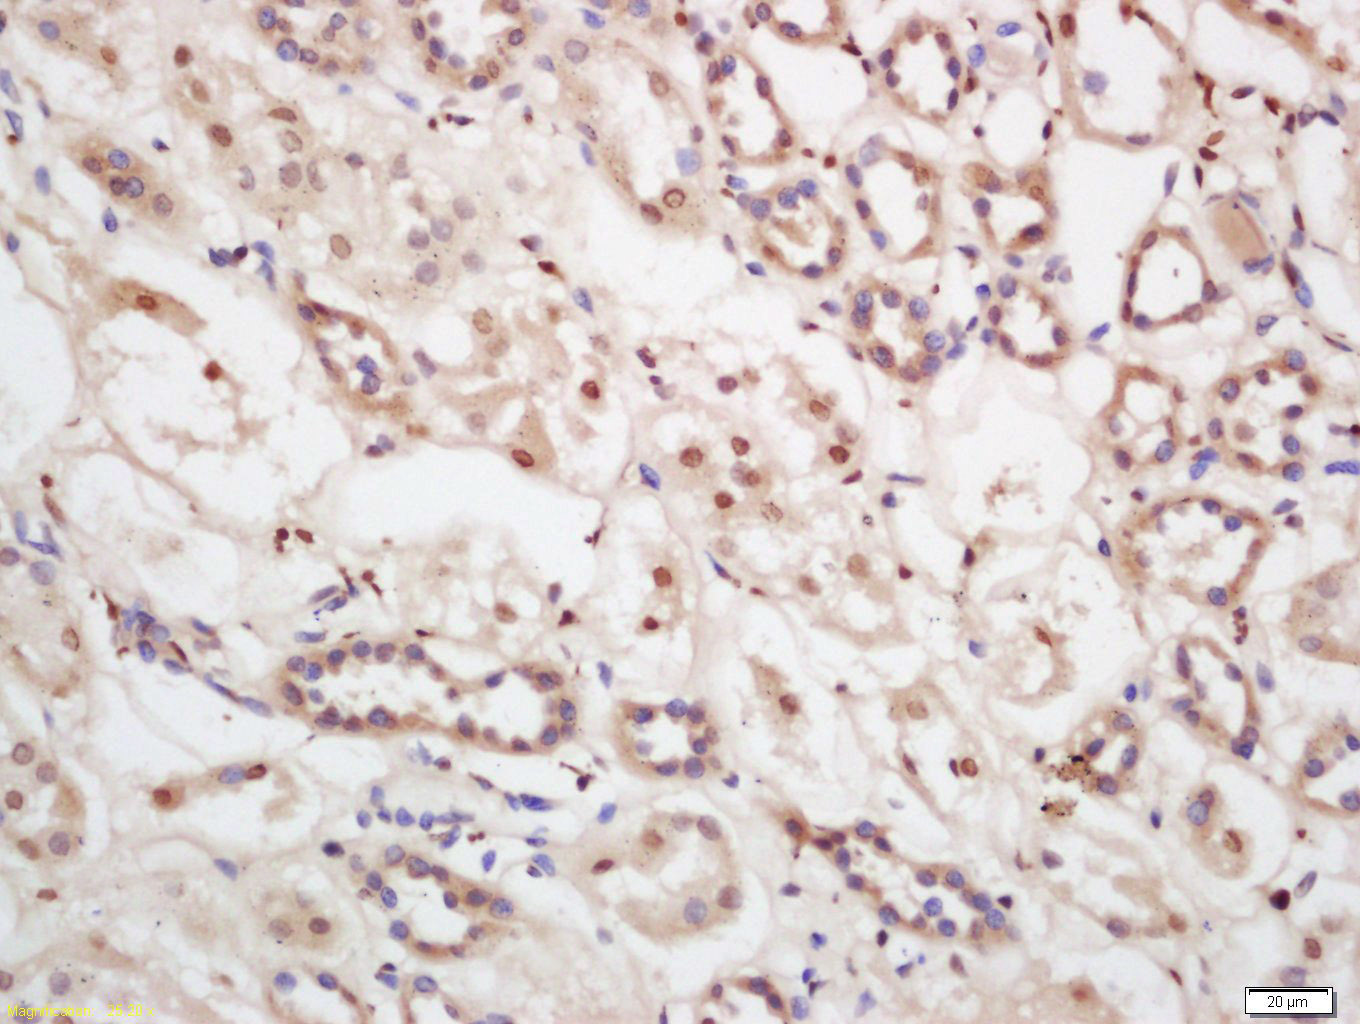

Tissue/cell: human kidney tissue; 4% Paraformaldehyde-fixed and paraffin-embedded; Antigen retrieval: citrate buffer ( 0.01M, pH 6.0 ), Boiling bathing for 15min; Block endogenous peroxidase by 3% Hydrogen peroxide for 30min; Blocking buffer (normal goat serum,C-0005) at 37℃ for 20 min; Incubation: Anti-TIAF1 Polyclonal Antibody, Unconjugated(bs-7602R) 1:200, overnight at 4°C, followed by conjugation to the secondary antibody(SP-0023) and DAB(C-0010) staining